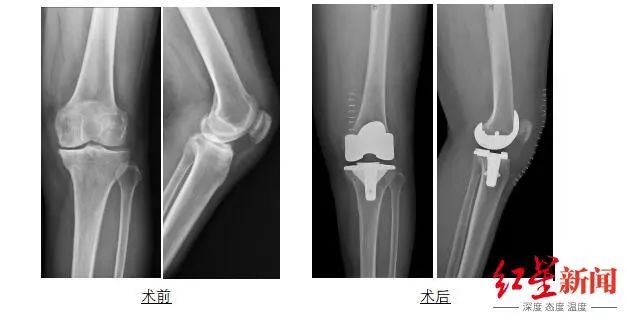

术前术后对比

周宗科教授对吴婆婆进行了全面的评估:跛行步态,双膝疼痛严重,活动受限伴有屈曲内翻畸形;X线片显示关节间隙狭窄,呈“骨磨骨”表现,膝关节周围骨赘形成;双膝骨关节炎已经到达终末期,左膝为重,只有通过手术治疗才能解决患者的病痛。

9月30日下午,周宗科教授团队成功为吴婆婆施行了左膝关节置换术,术中植入生物型膝关节假体时无需骨水泥对假体进行固定,手术时间得到明显缩短。术后X线片显示,假体与骨完美匹配,固定良好,位置正常,吴婆婆左膝畸形得到完全纠正,膝关节活动度好。困扰吴婆婆多年的膝盖问题终于得到解决。